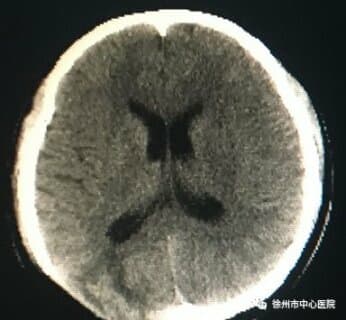

志愿者杨笑的女儿被诊断为脑积水,鼓楼区红十字会送上2000元救助金。